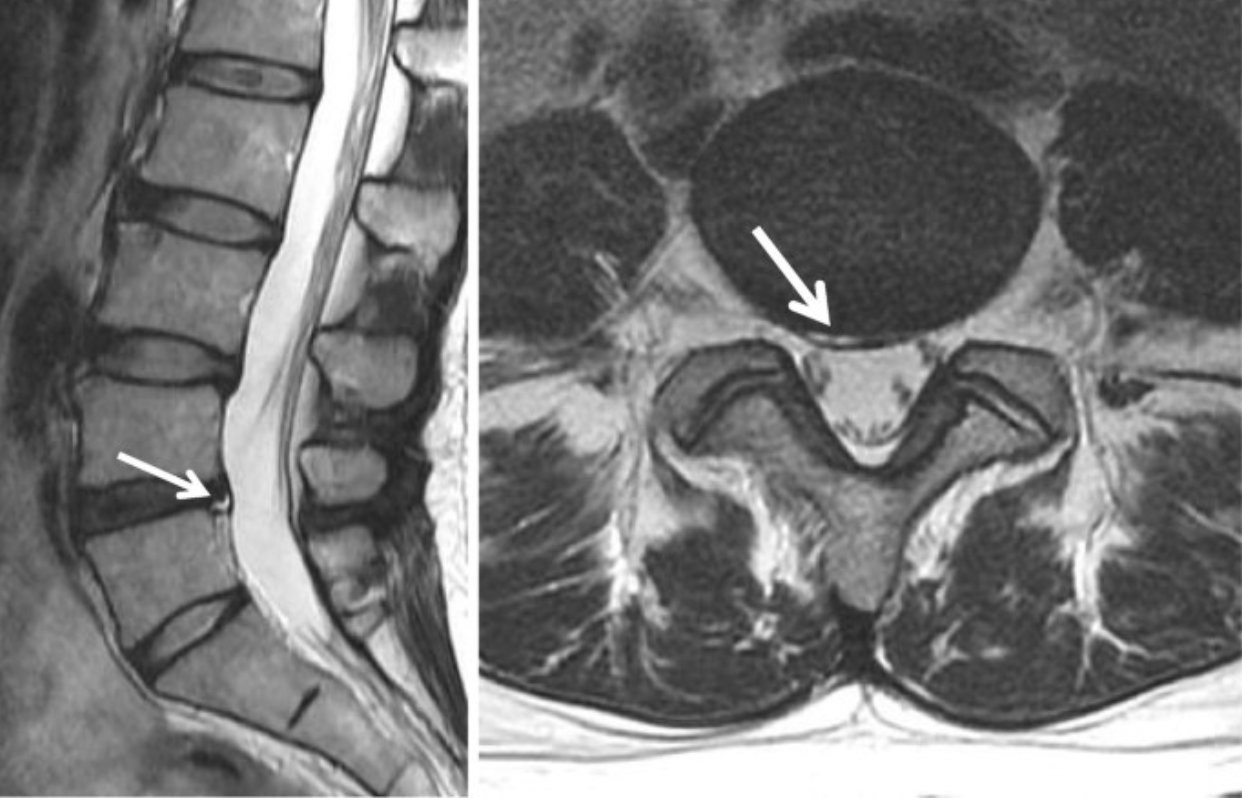

The High-Intensity Zone (HIZ) is defined as a focal area of increased signal intensity within the posterior annulus fibrosus on T2-weighted MRI that is clearly distinct from the nucleus pulposus. It represents an annular fissure/tear and is strongly associated with discogenic low-back pain, particularly when concordant with patient symptoms.

• Scroll through the mid-sagittal and parasagittal T2 sequences of the lumbar spine.

• Identify a well-defined hyperintense focus located within the posterior annulus fibrosus, separate from the nucleus pulposus.

• Appears on at least two adjacent slices, and

• Is brighter than nucleus pulposus on T2-weighted imaging.